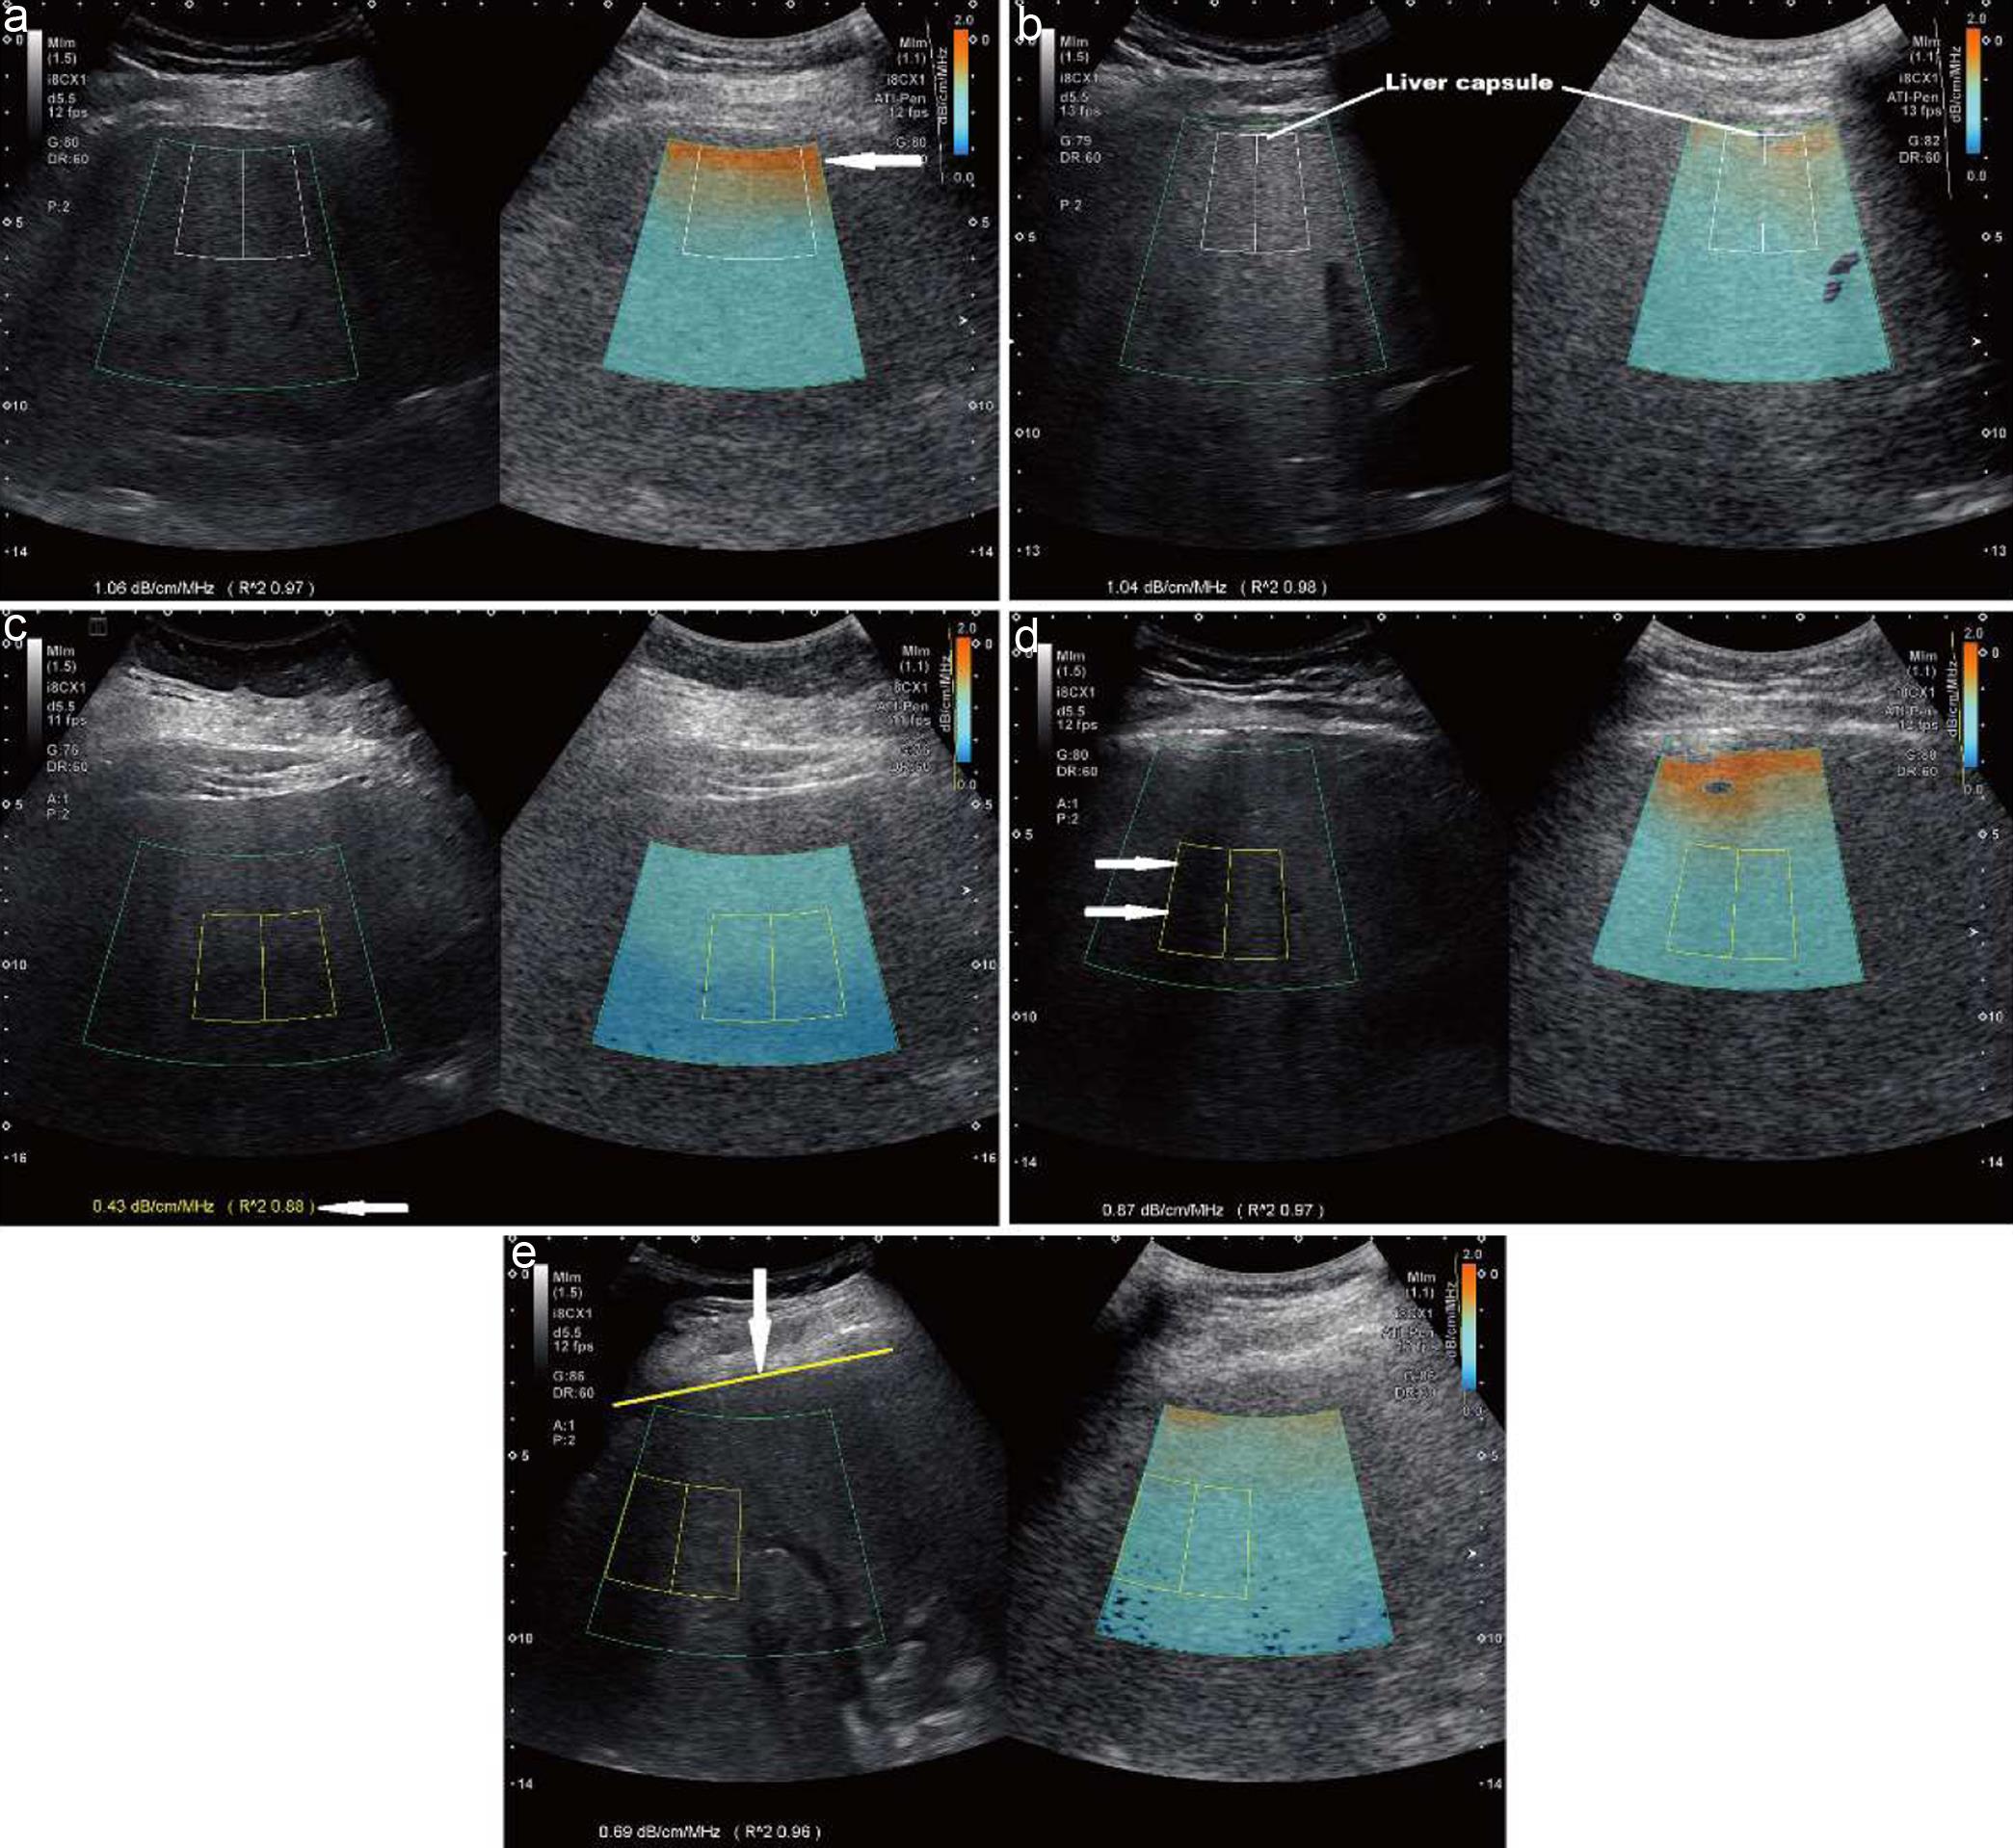

Ultrasound attenuation imaging

Re-measurements of the liver AC were performed by two junior operators (C.A. and J.D.) who had training in abdominal ultrasound (2 years) and received instruction on how to measure attenuation coefficient of the liver. These two junior operators were blinded to the initial study results of liver AC, MRI-PDFF, and clinical information of the participants. Using the image review function on the ultrasound scanner (Aplio i800, Canon Medical Systems USA), each of 5 ATI images recorded for each liver in the initial scans was selected and displayed on the screen (one on one). The initial AC value and measurement ROI were automatically deleted once the AC measurement function was activated. As a result, a new AC value can be measured by manually placing a region of interest (ROI) in color-coded ATI image. The site of ROI placement for measuring liver AC was confirmed by both operators. The protocol for re-measuring AC of the liver with variable size at different depths was standardized: using depth scales on the ultrasound image as a guidance, the operator manually placed a trapezoid ROI (3.0 cm tall by 3.0 cm wide) in the liver at the depth of 4.5 cm (the distance from the skin to the center of ROI, Fig. 1a), 6 cm (Fig. 1b), 7.5 cm (Fig. 1c), and a large ROI (6.5 cm tall, upper border wide 4 cm, and lower border wide 7.3 cm) that encompassed the entire color-coded region on the ATI image (Fig. 1d). Five ATI images per participant were reviewed. The average of 5 AC values at each depth in the liver were used for analysis. The quality of each AC measurement was evaluated by the R2 (coefficient of determination) value showed on the screen (Fig. 1a). AC measurements with R2 < 0.90 were categorized as measurement failure. All measurements were then logged in a Microsoft Excel spread sheet for analysis.

Ultrasound attenuation coefficient (AC, dB/cm/MHz) is measured using two sizes of the region of interest (ROI).

Fig. 1  Ultrasound attenuation coefficient (AC, dB/cm/MHz) is measured using two sizes of the region of interest (ROI).

A ROI (3 cm tall × 3 cm wide) is placed at the depths of 4.5 cm (the distance from the skin to the center of ROI (a), 6 cm (b), and 7.5 cm (c) in the liver. A larger ROI (d), 6.5 cm tall, 4 cm top border, and 7.3 cm of bottom border) is also used to measure AC of the liver. The AC value is 1.06 dB/cm/MHz, 0.86 dB/cm/MHz, 0.66 dB/cm/MHz, and 0.85 dB/cm/MHz measured at the depths of 4.5 cm, 6 cm, 7.5 cm, and with a large ROI, respectively. AC, attenuation coefficient; ROI, region of interest.

In the study, the best ROI depth for measuring liver AC is at 6 cm from the skin (Fig. 1b) resulting in the highest diagnostic performance of AC to determine ≥ mild hepatic steatosis, ATI quality, and lowest failure rate compared with AC values measured at depths of 4.5 cm, 7.5 cm, and large ROI. The ROI depth at 4.5 cm seemed to be too close to the liver capsule to avoid the dark orange color area produced by high noise or reverberation artifact (Fig. 4a, b) in some patients. The ROI depth at 7.5 cm was often too deep from the skin to exclude the dark blue area (weak echo signal, Fig. 4c) due to less sound penetration,19 which yielded the poor ATI quality, low diagnostic performance, and high failure rate. The utilization of a large ROI is able to assess tissue attenuation in relative larger region of liver parenchyma (6.5 cm × 7.3 cm vs. 3 cm × 3 cm). However, using a large ROI to measure liver AC magnifies technical challenges to place such a large ROI in a small liver (such as a cirrhotic liver) and avoid prominent hepatic vessels (e.g. dilatation of the hepatic veins in congestive heart failure or portal vein in significant portal hypertension). Further, AC measured at the depth of 7.5 failed to distinguish steatotic livers from normal livers as the difference in AC value between normal and steatotic livers was not significant (p = 0.10, Table 1).